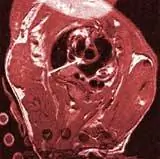

Ученые из Вюрцбургского университета впервые с помощью магнитного резонанса (МР) сделали видимым кальцификацию кровеносных сосудов у живых мышей. Изображения также показывают изменения, связанные с атеросклерозом.

Артериосклероз, также известный как кальцификация кровеносных сосудов, сначала развивается в областях аорты, которые очень близки к сердцу. Врачам и биофизикам из Вюрцбургского университета впервые удалось визуализировать эти участки аорты у живых мышей с помощью магнитного резонанса.

Ученые из Вюрцбурга использовали мышей, у которых отсутствует ключевой ген метаболизма холестерина. Это автоматически создает артериосклеротические отложения (бляшки) в кровеносных сосудах животных, которые очень похожи на таковые у людей. Этот процесс обычно начинается в корне аорты, восходящей аорте и дуге аорты.

Исследователь из клиники медицинского университета разработал этот метод в сотрудничестве с кафедрой биофизики Вюрцбурга. Благодаря «последовательности спин-эхо высокого разрешения» впервые были получены изображения атеросклеротических бляшек живой мыши. По словам Висмана, качество изображений настолько хорошее, что стенка сосуда и внутренняя часть аорты могут быть отображены в мельчайших деталях как в области груди, так и в области живота.